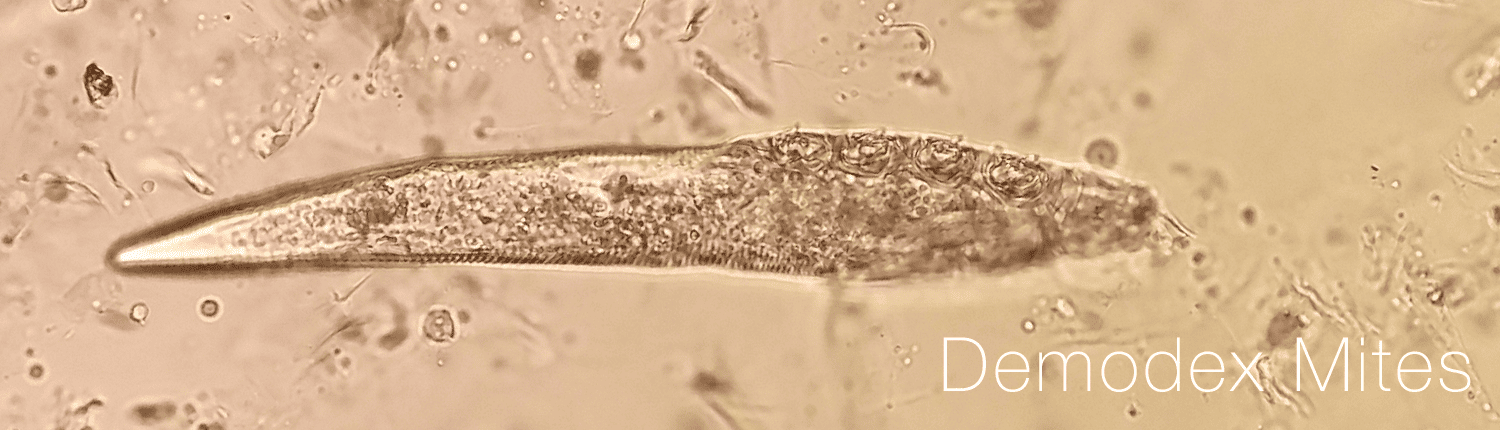

Demodex mites are tiny, worm-like parasites that live on the skin, including the skin around the eyes. There are two main species of Demodex mites that affect humans: Demodex folliculorum and Demodex brevis. Demodex folliculorum are typically found in the hair follicles and sebaceous glands of the skin, while Demodex brevis are typically found in the meibomian glands (glands that produce oil to keep the surface of the eye lubricated) and the sebaceous glands of the eyelids.

Demodex mites are usually harmless and do not cause any symptoms. However, in some people, infestations of Demodex mites can lead to a variety of problems, including dry eye, eye irritation, and inflammation of the eyelids. Demodex mites are more common in people with certain risk factors, such as advanced age, a history of eye surgery, and certain medical conditions, such as rosacea (a skin condition that affects the face).

Treatment for Demodex mites may involve the use of medications or topical ointments to kill the mites and reduce inflammation. In many cases, treatment may also include using eyelid hygiene products to clean the eyelids and remove debris.

Additional treatment procedures may be available. It is important to schedule an appointment with us if you have symptoms of an infestation of Demodex mites, as early diagnosis and treatment can help to prevent complications and preserve vision.

Demodex mites are usually harmless and do not cause any symptoms. However, in some people, infestations of Demodex mites can lead to a variety of problems, including dry eye, eye irritation, and inflammation of the eyelids. Demodex mites are more common in people with certain risk factors, such as advanced age, a history of eye surgery, and certain medical conditions, such as rosacea (a skin condition that affects the face).

Treatment for Demodex mites may involve the use of medications or topical ointments to kill the mites and reduce inflammation. In many cases, treatment may also include using eyelid hygiene products to clean the eyelids and remove debris.

Additional treatment procedures may be available. It is important to schedule an appointment with us if you have symptoms of an infestation of Demodex mites, as early diagnosis and treatment can help to prevent complications and preserve vision.